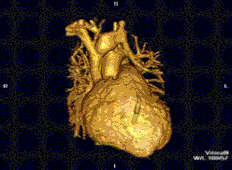

Cardiovascular

Cardiac MRI is complementary to other imaging techniques, such as echocardiography, cardiac CT, and nuclear medicine. It can be used to assess the structure and the function of the heart.[30] Its applications include assessment of myocardial ischemia and viability, cardiomyopathies, myocarditis, iron overload, vascular diseases, and congenital heart disease.[31]